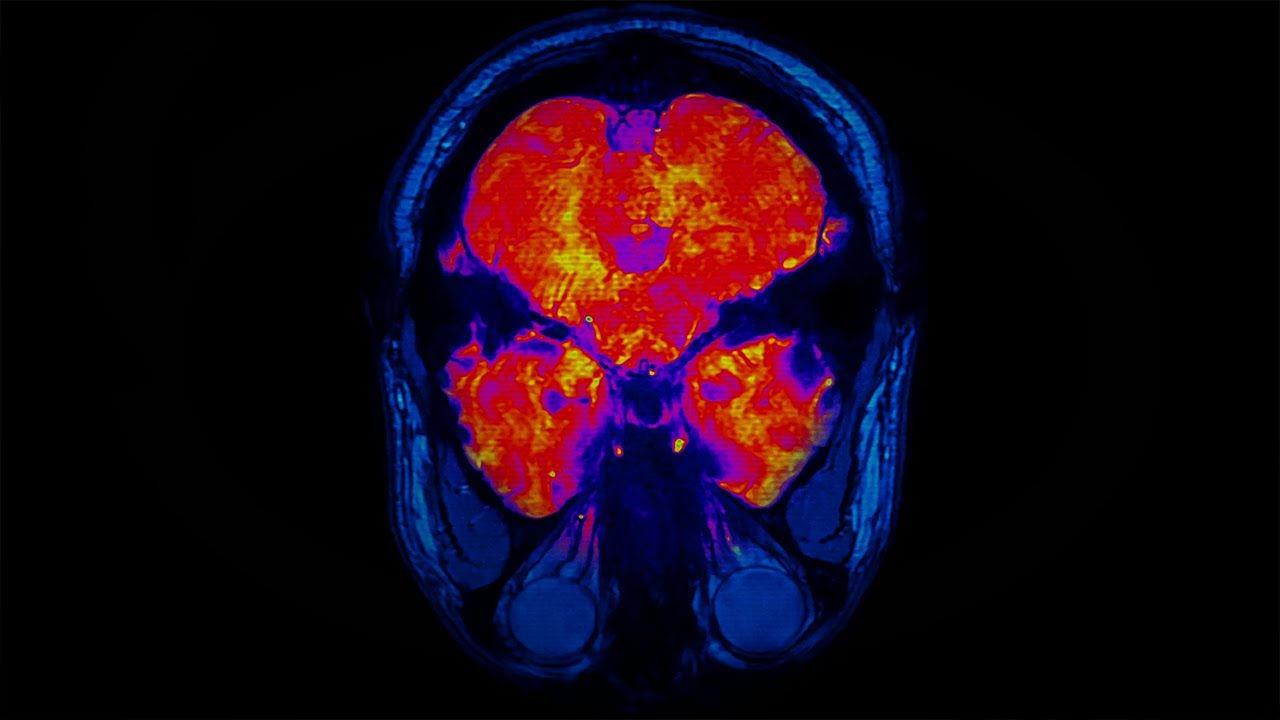

How aging degrades neural functioning in the brain over time

Aging affects the brain perhaps more than any other organ in the body. Throughout life, the brain experiences radical shifts in the number of neurons, synaptic connections between neurons, and hormone levels that regulate our mood and processing.